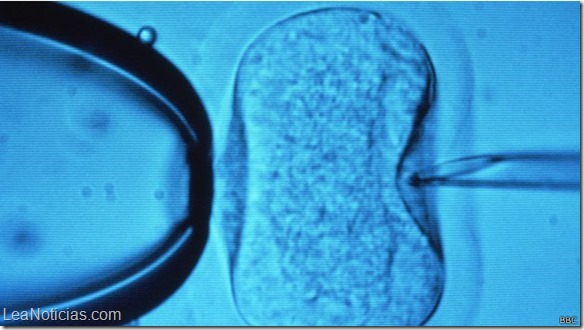

Al día siguiente, este tubo de ensayo pasa por un microscopio para ver si contiene un embrión, lo que significa que la fertilización del óvulo tuvo lugar.

Si se crea un embrión de forma exitosa, se transfiere desde el tubo de ensayo hasta el útero de la mujer después de unos seis días.

Los ensayos comenzaron en Genk, Bélgica, en 2012 y hasta el momento 17 bebés sanos han nacido con este sistema.

Ombelet está encantado con los resultados preliminares que muestran que esta fertilización y las tasas de embarazo son similares a los métodos estándar de fecundación in vitro.

«Hemos demostrado que con nuestro sistema la calidad embrionaria es tan buena como con la FIV regular”.